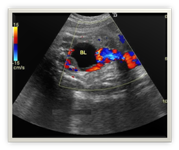

What abnormality of the placenta is affecting this late second-trimester pregnancy?